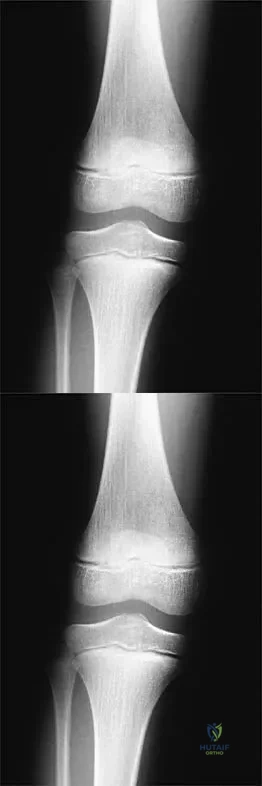

Figure 24 shows the radiograph of a 10-year-old boy who sustained a valgus injury to the knee. Examination reveals grade III medial laxity. Initial management should consist of

A right-handed 14-year-old pitcher has had a 3-month history of shoulder pain while pitching. Examination reveals full range of motion, a mildly positive impingement sign, pain with rotational movement, and no instability. Plain AP radiographs of both shoulders are shown in Figures 25a and 25b. Management should consist of